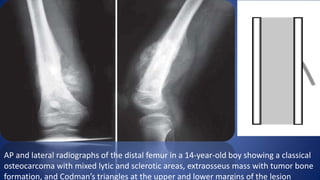

AP and lateral radiographs of the distal femur in a 14-year-old boy showing a classical

osteocarcoma with mixed lytic and sclerotic areas, extraosseus mass with tumor bone

formation, and Codman’s triangles at the upper and lower margins of the lesion